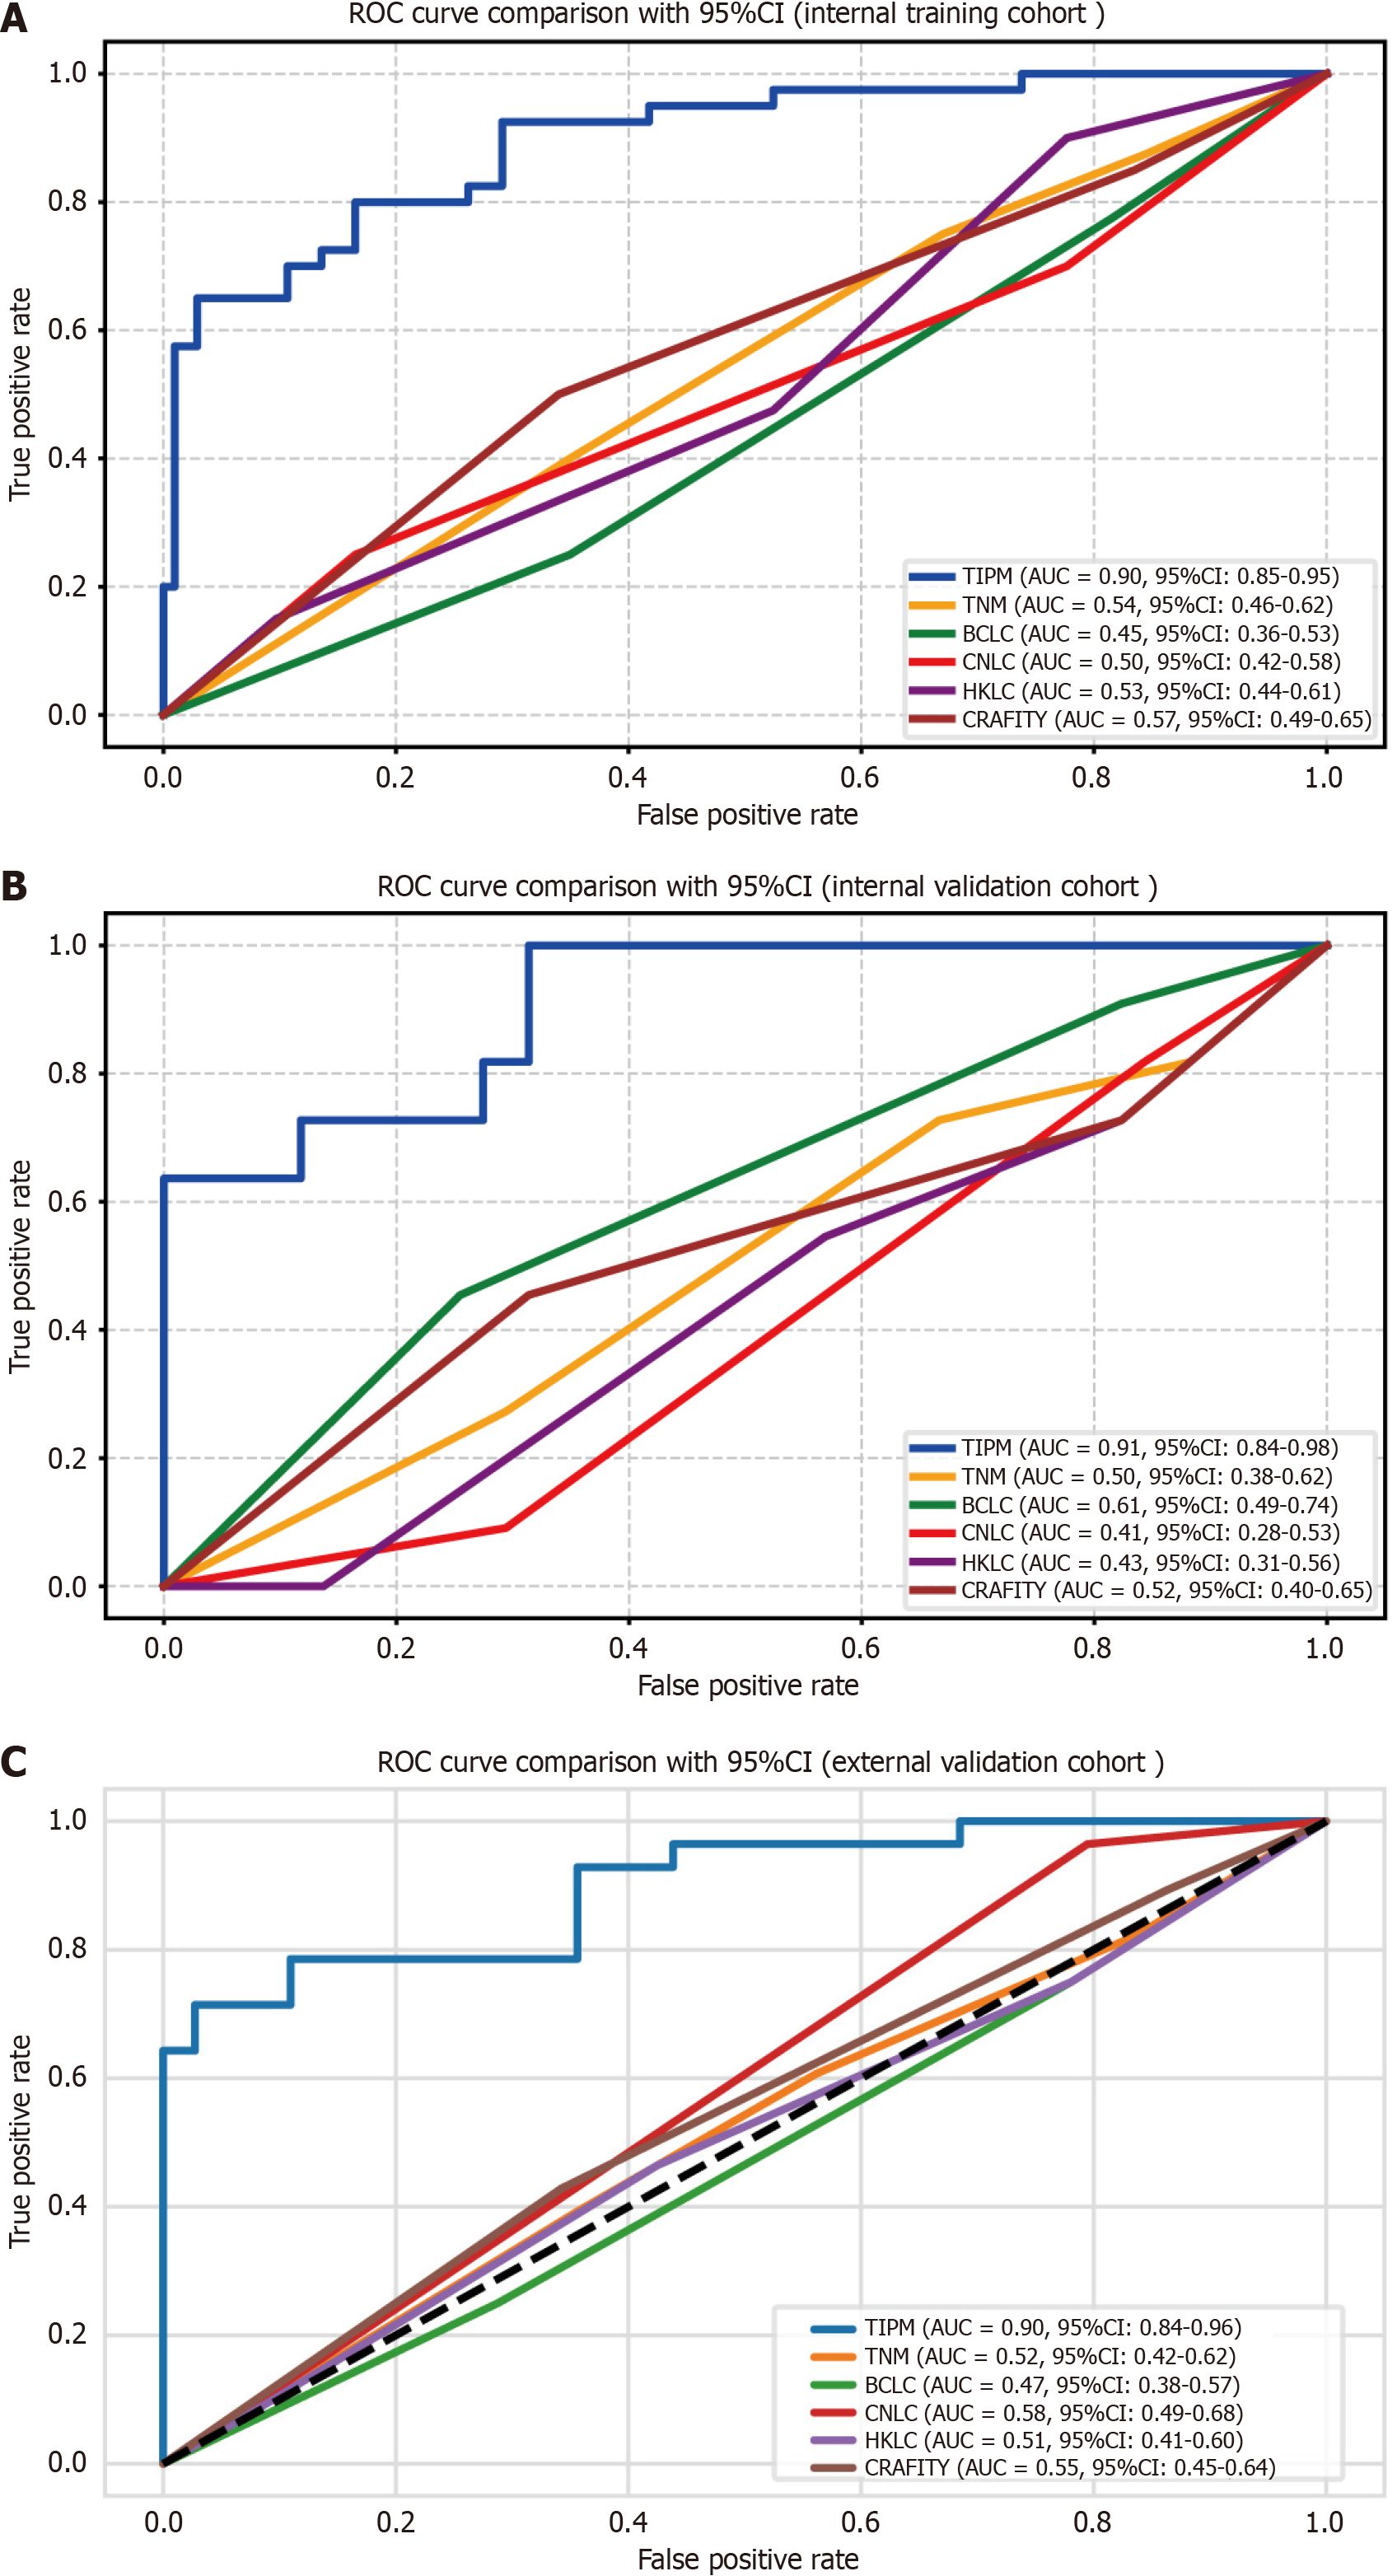

Figure 4 Receiver operating characteristic curves for the Target Immunotherapy Predictive Model and comparator models.

A: Internal training cohort shows Target Immunotherapy Predictive Model (TIPM) achieving superior discrimination with an area under the curve (AUC) of 0.895; B: Internal validation cohort demonstrates TIPM maintaining the highest predictive performance (AUC 0.907) compared to alternative models; C: External validation cohort confirms TIPM’s consistent discriminative advantage (AUC 0.899). All curves illustrate TIPM’s robust performance superiority across different patient populations. ROC: Receiver operating characteristic; AUC: Area under the curve; TIPM: Target Immunotherapy Predictive Model; TNM: Tumor-node-metastasis; BCLC: Barcelona Clinic Liver Cancer; CNLC: China Liver Cancer; HKLC: Hong Kong Liver Cancer; CRAFITY: C-reactive protein and alpha-fetoprotein in immunotherapy.